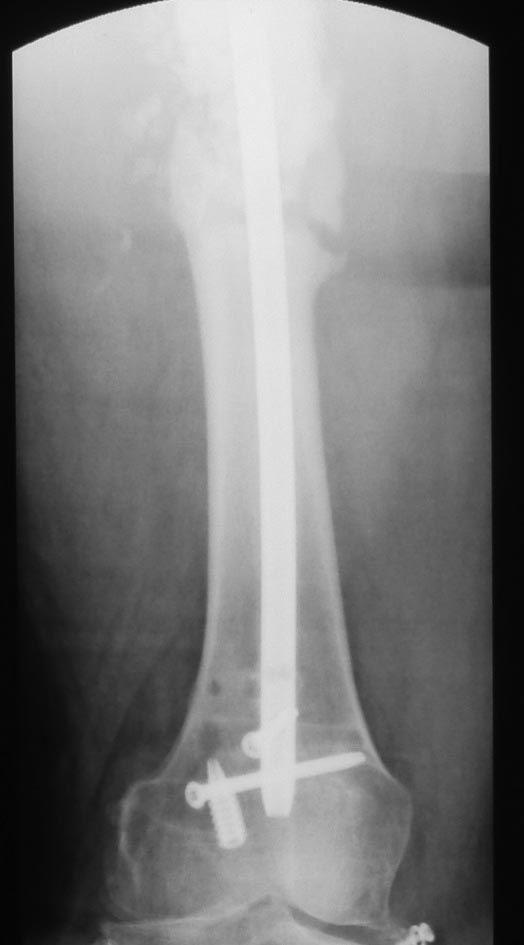

Уважаемые коллеги. Хотелось бы выслушать мнения и советы по представленному случаю. Пациент 42 лет, вес 130 кг, рост около 160 см, сахарный диабет в легкой форме (впервые выявлен после травмы). Травма в феврале 2011 г. - упал с мотоцикла на отдыхе за рубежом. По возвращении в Россию был прооперирован в несколько этапов: в марте 2011 г. - остеосинтез обеих костей правого предплечья пластинами по поводу открытого перелома; интрамедуллярный остеосинтез правого бедра; остеосинтез проксимального конца правой большеберцовой кости. В апреле 2011 г. был доставлен 1 блокирующий винт в дистальное отверстие гвоздя и выполнена пластика крестообразных и наружной боковой связок левого коленного сустава. В феврале 2012 г. были удалены фиксаторы с проксимального конца правой большеберцовой кости и выполнена пластика крестообразных и наружной боковой связок правого коленного сустава. За это время пациент смог начать ходить, сначала с костылями, а затем - без дополнительной опоры. Летом 2013 г. решил укрепить ноги с помощью подъемов пешком на пятый этаж. В результате - усталостная рефрактура правого бедра и перелом интрамедуллярного гвоздя. 09.09.2013 - реостеосинтез латеральным бедренным гвоздем с пластикой костной аутостружкой + СhronoS. Сейчас, через 6 мес после операции, может ходить без дополнительной опоры, периодически беспокоит болезненность в области правого бедра. На сегодняшних КТ - отсутствие признаков консолидации. Нужно ли что то делать и, если да, то что? Рассматриваемые варианты: повторная костная пластика дефекта; доставить блокирующие винты (самый проксимальный винт был удален через 3 мес после операции). Еще раз менять гвоздь не хотелось бы. На представленных снимках: бедро в 2011 г., через несколько мес после операции; в 2012 г., на стадии консолидации; со сломанным гвоздем; сразу после повторной операции (3 рентгенограммы). Все КТ - сегодняшние. Заранее спасибо за ответы.

Согласен, стержень тонковат в дистальном отломке. Если совсем никак не возможно перепровести с рассверливанием более толстый стержень, можно согласиться с вашим предложением ввести еще один винт в дистальный конец гвоздя, но полностью убрать винты из проксимального отломка, чтобы перенести осевую нагрузку на кость и не опасаться перелома гвоздя или винтов.

Насколько это эффективно в отношении консолидации будет видно примерно через 6 недель. Незабудьте сделать, если его нет, обычный свежий снимок до динамизации для последующего сравнения.